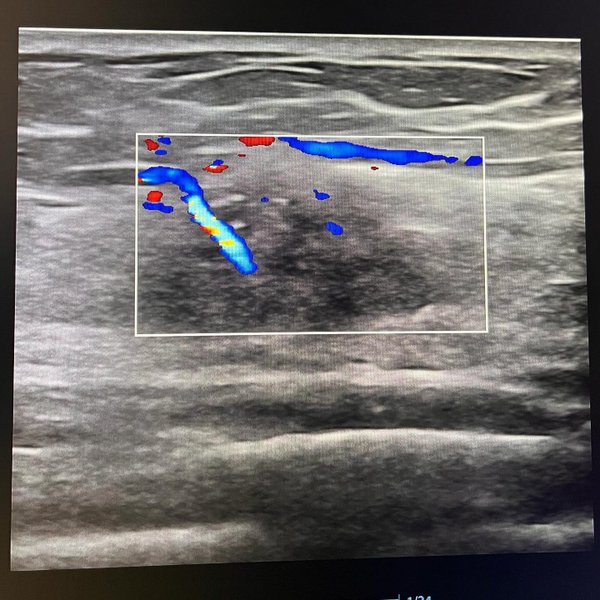

УЗИ-диагностика. ️по записи БЕЗ очереди.. Запись по тел. или по кнопке «Записаться» --- Бородулина Наталья (Врач УЗИ, Косметология) (26.01.2026): #УЗДГ маточных артерий при #беременности: зачем нужен этот «доплер»? Многие слышали, но не все понимают, зачем его назначают. Объясняем коротко и ясно! Что это Специальное #УЗИ с #доплером, которое оценивает не ребенка, а ️кровоток в сосудах, питающих матку и плаценту. Проще говоря, смотрим, насколько хорошо малыш снабжается кислородом и питанием. ‼️3 главные причины сделать: 1️⃣Ранняя профилакти… — Читать дальше

ка. Поможет предсказать риски гестоза, преэклампсии, задержки роста плода (ЗВУР) задолго до появления симптомов. 2️⃣Контроль. Если есть хронические болезни (гипертония, диабет) — это обязательный пункт наблюдения. 3️⃣Спокойствие. Нормальные показатели — это уверенность, что плацентарный кровоток в полном порядке. Как проходит Так же, как и обычное УЗИ. Никакой боли и дискомфорта. Длится 10—15 минут. Когда делать? Чаще всего в 20—24 недели (второй скрининг), но при показаниях — и раньше, и чаще. Это исследование — ваш союзник в рождении здорового малыша ️.

#УЗДГ маточных артерий при #беременности: зачем нужен этот «доплер»?

Что это Специальное #УЗИ с #доплером, которое оценивает не ребенка, а ️кровоток в сосудах, питающих матку и плаценту. Проще говоря, смотрим, насколько хорошо малыш снабжается кислородом и питанием.

2️⃣Контроль. Если есть хронические болезни (гипертония, диабет) — это обязательный пункт наблюдения.

3️⃣Спокойствие. Нормальные показатели — это уверенность, что плацентарный кровоток в полном порядке.

Как проходит Так же, как и обычное УЗИ. Никакой боли и дискомфорта. Длится 10—15 минут.

Когда делать? Чаще всего в 20—24 недели (второй скрининг), но при показаниях — и раньше, и чаще.

Это исследование — ваш союзник в рождении здорового малыша ️.